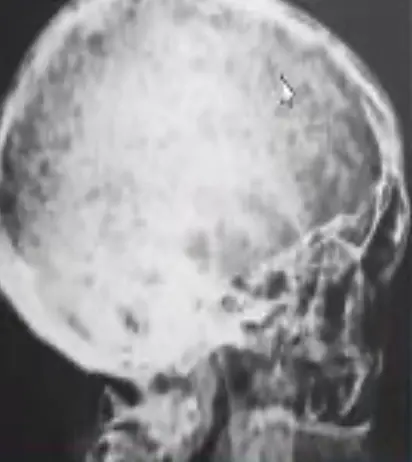

Fat Embolism Case

A 32-year-old man who had sustained a traumatic fracture of the left femoral shaft 20 hours earlier was referred for a sudden deterioration of consciousness. He was unresponsive to verbal stimuli but no focal neurologic abnormalities were found.

Q1. What is the most probable diagnosis?

- Fat embolism (petechial hemorrhage)

Q2: What is the treatment of choice?

- Respiratory support, early recognition, call the anesthesia and transfer to ICU